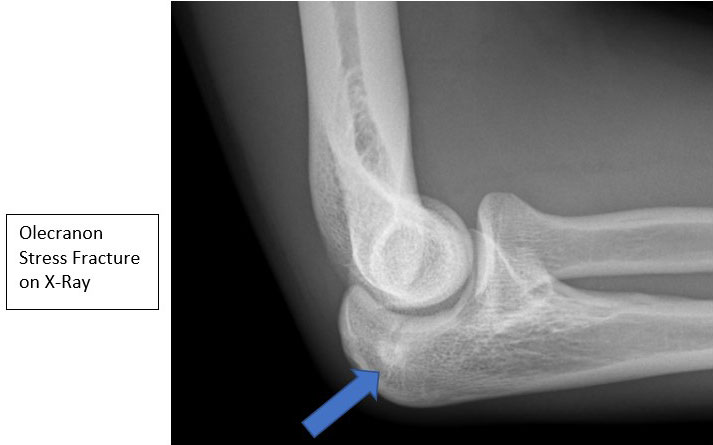

- Radiographs may demonstrate linear sclerosis, fracture lines, or periosteal bone formation. Contralateral films can help determine amount of closure

- MRI, CT and Bone scan can help establish diagnosis if x-rays are normal